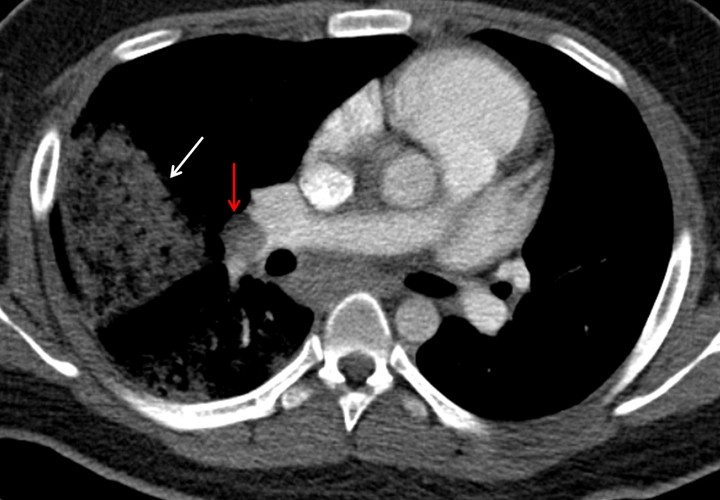

患者肺栓塞ct可见右肺动脉主干栓塞(红色箭头)及大面积肺梗死